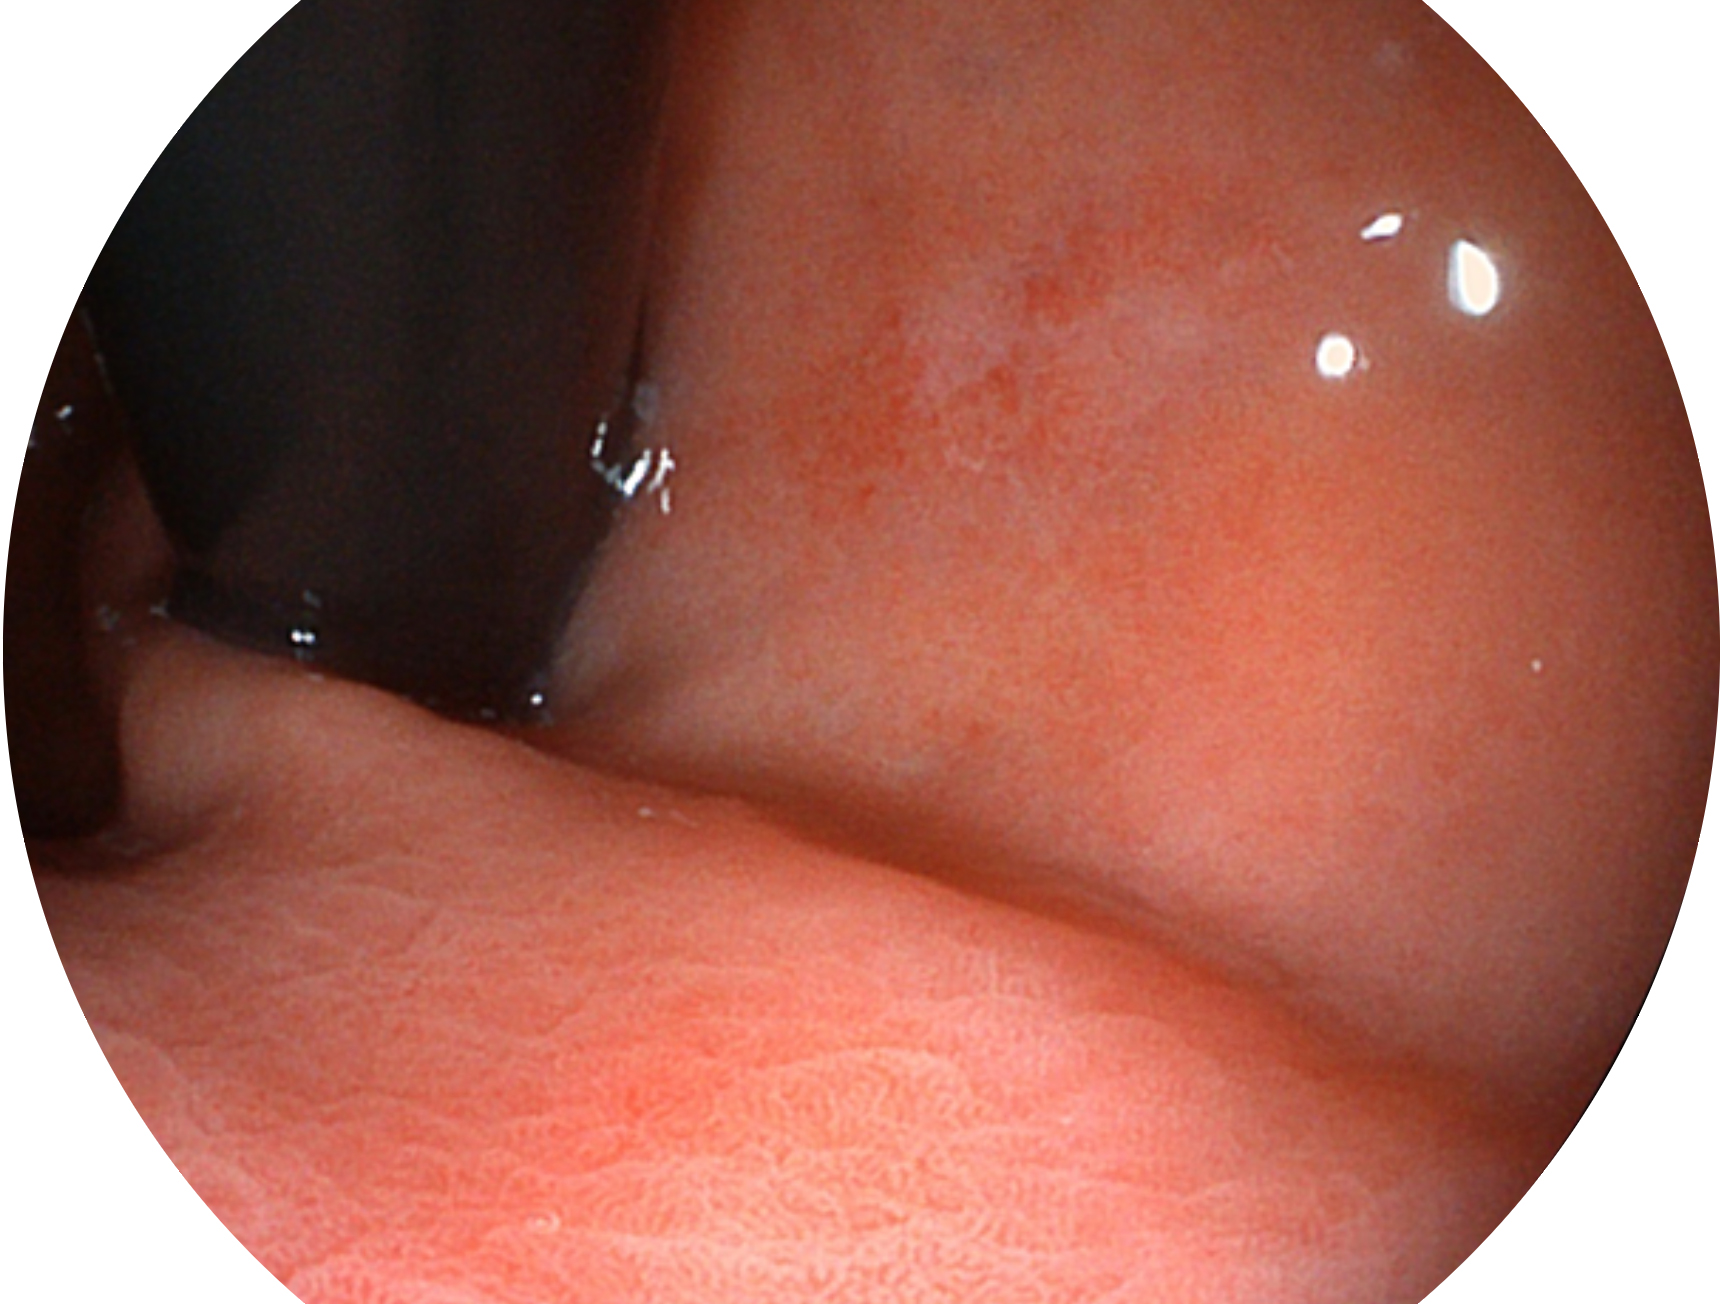

百老汇电子游戏官网新开发的内镜染色技术,主要是基于多波长LED 光源的开发,VLS-55Q 四波长LED 光源是由四个不同颜色的LED光按照相应照明模式所规定的特定发光比例进行合束后形成,合束后形成的照明光的光谱由红光、绿光、蓝光及蓝紫光这四个不同的波段范围构成。具有更高光谱自由度,通过光谱比例的控制,实现了聚谱成像技术,英文全称为“Spectral Focused Imaging, SFI”,缩写为“SFI”和光电复合染色成像技术,英文全称为“Versatile Intelligent Staining Technology, VIST”,缩写为“VIST”。